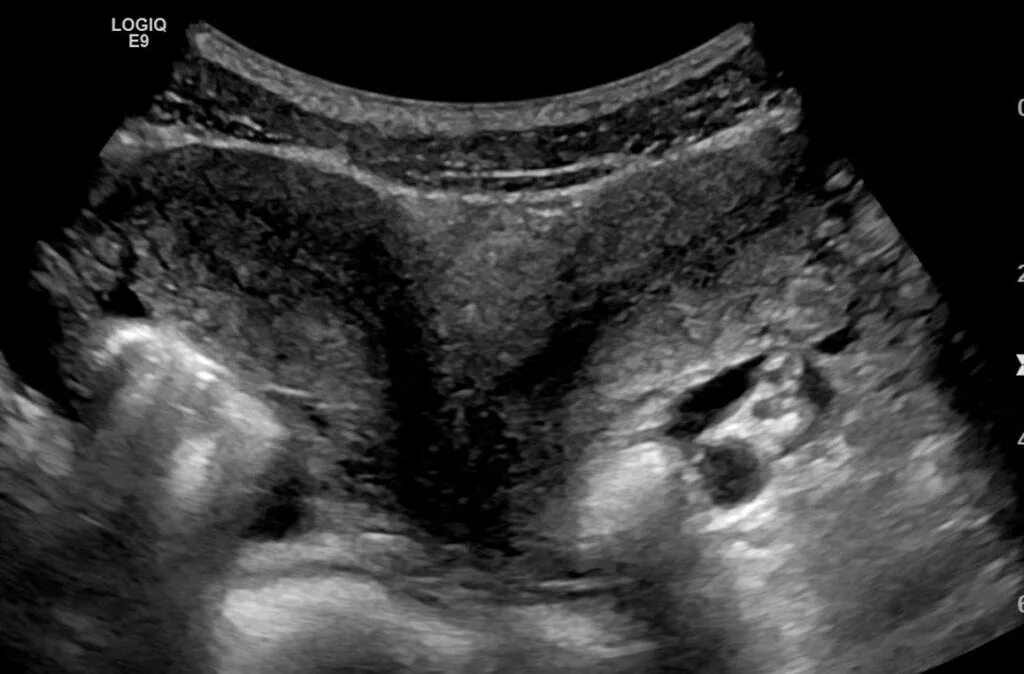

Как выглядят 2 матки